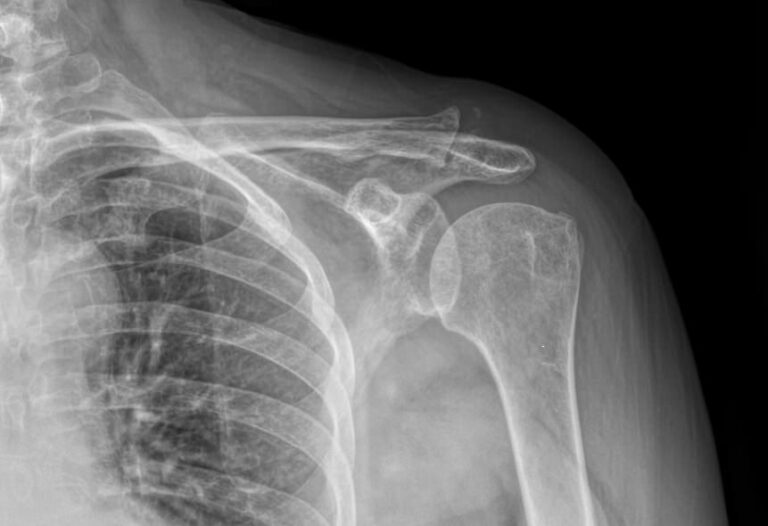

В случае травмы на снимке могут быть обнаружены:

• Отек мягких тканей;

• Расширение суставной щели;

• Ключица приподнята над акромионом;

• Перелом ключицы или клювовидного отростка лопатки;

• Изменения, свойственные дегенеративным процессам костной ткани.